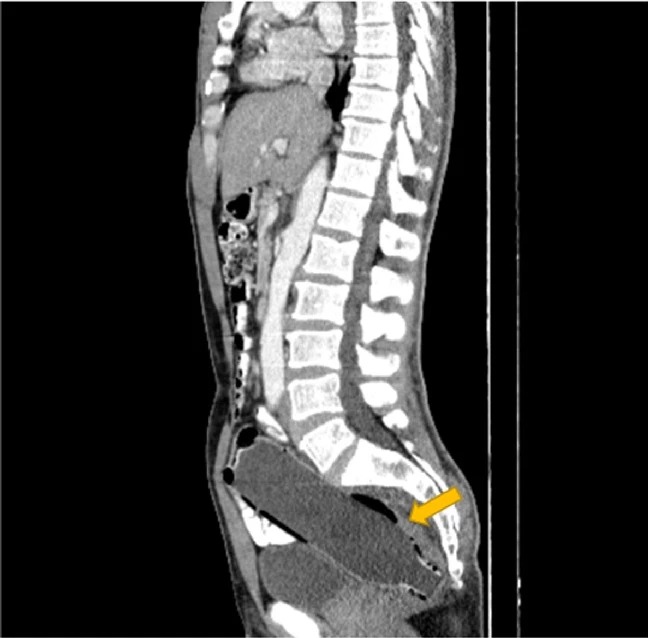

Se trata de un hombre iraní que padeció de un dolor abdominal por días, hasta que le dijo a su esposa que fueran al médico para saber a qué se debía. La sorpresa fue cuando le hicieron una tomografía en la cual se veía un objeto extraño en el intestino grueso del paciente.

Según un artículo de la Clínica Case Reports Journal, el hombre evitó mencionar que él mismo había insertado una botella plástica por el recto, debido a la "vergüenza" y al "miedo a su esposa".

El hombre duró tres días con la botella dentro suyo, cabe mencionar que el objeto tenía un a tamaño de 20 centímetros de largo.

“La base de la botella estaba en la región proximal del colon y la abertura de la botella estaba cerca del ano”, agregó el documento médico.